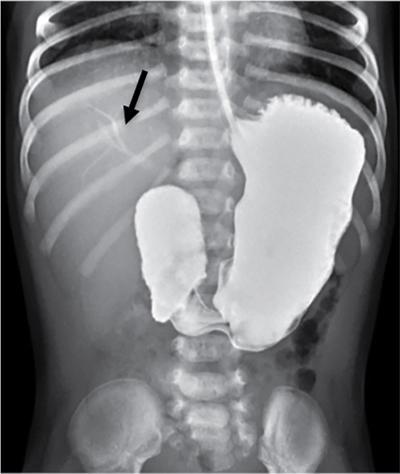

C.V. Kanimozhi, S. Muralinath, Raveendran J. Many of the important congenital gastrointestinal abnormalities present acutely in the newborn; some present much later. These include obstructive gastrointestinal lesions that present with vomiting, abdominal distension and not having passed meconium. The imaging modalities that are most commonly used in the evaluation of neonatal gastrointestinal abnormalities are plain films, contrast studies and ultrasound. Plain films remain a valuable tool in the assessment of abdominal abnormalities in the neonate. They are also an excellent guide to determining the next proper imaging study to perform for a particular problem. Certain neonatal bowel disorders have a pathognomonic appearance on radiographs obviating the need for further imaging. The essential and basic view to be done at the bedside is the supine view of the abdomen. In the evaluation of abnormal intra-abdominal gas patterns, alternative decubitus views, prone and supine cross-table lateral views may be taken. Erect view is not utilized in neonatal practice at the bedside as it is impossible to restrain a neonate in that position and unnecessarily subjects the neonate to stress, which may worsen the condition of an already sick baby. Evaluation of the bowel gas pattern and the anatomic localization of the intra-abdominal gas is the key to diagnosis in the evaluation of diseases of the GI tract. The bowel gas in the neonate is essentially swallowed air (Box 7.8.1). Movement of Air Through the GIT in a Term Neonate Most infants pass meconium by 24 hours of life. In order to interpret the bowel gas pattern and determine if an abnormality is present, it is crucial to know the age of the neonate (hours since birth) at the time the radiograph was taken. When there is impaired swallowing, such as due to CNS depression or in prematurity, radiographs show diminished bowel gas. In cases of bowel atresia, radiographs show absence of bowel gas in distal segments. Thus, the distribution of bowel gas and its pattern serve as pointers to the diagnosis. After the radiograph has been done, depending on the findings, an ultrasound or fluoroscopic contrast study may be performed next. The radiologist should tailor the contrast study to suit the particular patient and the clinical question that needs to be answered. In cases of suspected high GI obstruction, an upper GI contrast series is study of choice; in cases of suspected low GI obstruction a contrast enema should be performed to delineate the anatomy. When performing fluoroscopic studies, it is important to bear in mind the radiation dose and to adopt the ALARA principle. Minimizing radiation exposure in children is important because they are more sensitive to the effects of radiation and have a longer life expectancy than adults. The technical parameters must be adapted to paediatric imaging. Ultrasound is a useful bedside tool particularly in the sick neonate. In neonates, the sonographic image resolution is excellent due to the lack of significant body fat. In neonates, exquisite images of the abdomen can be obtained with the high-resolution ultrasound probe, which permits imaging the bowel wall in great detail. In addition, it can also reveal other causes for abdominal distension or vomiting. In this chapter, we will discuss the aetiology, clinical presentation and imaging appearances of congenital neonatal gastrointestinal abnormalities. We will also discuss common acquired abnormalities that present in the neonatal period, namely necrotizing enterocolitis. Congenital oesophageal malformations of the newborn include the various types of atresia (with and without fistula) and oesophageal duplications. Oesophageal atresia with or without tracheoesophageal fistula (TEF) is a common congenital anomaly that manifests in the neonatal period. It is also the most important congenital malformation of the oesophagus. Oesophageal atresia is commonly associated with other anomalies of the gastrointestinal tract such as imperforate anus, pyloric atresia, duodenal atresia and annular pancreas and less frequently with anomalies of the cardiac and genitourinary systems. About 20% of patients with oesophageal atresia have the VACTERL syndrome (vertebral anomaly, anorectal atresia, cardiac lesion, tracheoesophageal fistula, renal anomaly, limb defect). Oesophageal stenosis and webs may be associated with oesophageal atresia. The aetiology of oesophageal atresia and TEF is not completely understood. Faulty separation of the primitive trachea and oesophagus is the most widely accepted theory. The way the primitive foregut cleaves into a ventral (tracheal) passage and a dorsal (oesophageal) passage is a complex process and is poorly understood. Folds developing from the longitudinal ridge is said to separate the two. When the separation has an extreme tracheal bias, an oesophageal atresia occurs and if the bias is towards the oesophagus, then a tracheal atresia ensues. Incomplete separation may result in fistula of various types. Oesophageal atresia and TEF are classified depending upon the absence or presence and location of the fistula between the oesophagus and the trachea (Fig. 7.8.1). Neonates present within a few hours of birth with excessive salivation, drooling, cyanotic spells and regurgitation of feeds. The inability to successfully pass a nasogastric tube strongly suggests oesophageal atresia. Newborns with H-type fistula may have feeding difficulties and choking, but often the presentation and diagnosis is only later in infancy when the patient presents with cough, choking episodes and recurrent pneumonia. The role of imaging is to diagnose, define the anatomy to the best extent possible and evaluate for other anomalies to provide a clear picture for the paediatric surgeon. For example, it is important for the surgeon to know the side of the aortic arch in order to lateralize the surgical approach. Chest X-ray and Echo can localize the arch and determine if an anomalous right-sided aortic arch is present. Plain films of the chest including abdomen need to be obtained. The radiograph will demonstrate the air-filled distended proximal oesophageal pouch. If a nasogastric tube has been inserted, the coiled tube will be seen within the pouch. Absence of bowel gas in the abdomen indicates oesophageal atresia without a distal fistula – types A and B have this radiographic appearance (Fig. 7.8.2). The presence of gas in the gastrointestinal tract indicates the presence of a distal fistula – types C and D (Fig. 7.8.3). Contrast studies to delineate the proximal pouch are generally not indicated. Coiling of the nasogastric tube in the proximal pouch confirms the diagnosis. Chest radiographs frequently show changes of consolidation due to aspiration pneumonia, most often involving the right upper lobe (Fig. 7.8.4). In cases of H-type fistula, plain films are nonspecific and the diagnosis depends on contrast studies. Radiological diagnosis is made by means of a tube oesophagogram. This study has the potential risk of aspiration and the neonate may desaturate quite rapidly. Hence, it is important to have neonatal emergency resuscitation at hand. The tube oesophagogram is performed under fluoroscopy with the baby in lateral- or steep-prone oblique position. The NG tube is placed at the oesophagogastric junction and is gradually withdrawn while simultaneously injecting contrast. Nonionic low-osmolar contrast agent should be used. Most of the H-type fistulas are located in the lower cervical and upper thoracic regions with the fistula typically coursing upward and forward from the oesophagus. In the presence of a fistula, the contrast will be seen passing into the trachea in an upwardly oblique configuration. Aspiration during the study can also cause the contrast to appear in the tracheal tree and the lungs. It needs to be established whether the contrast has passed through the fistula or whether aspiration has occurred. Recording of the fluoroscopic run and reviewing the images may be required to make this distinction. Repeat examination may be required. Demonstration of H-type fistula can be difficult radiologically. In such patients, bronchoscopy with transfistula guidewire placement has been found to be of use. MRI – High resolution structural MRI is a new technique that is being used to visualize tracheobronchial anatomy. The disadvantage with radiographs is that one cannot determine the anatomic subtype of TEF, the site of the TEF or the length of the gap between the atretic segments. Using ultrashort echotime (UTE) MR imaging, it is possible to visualize the exact site of the fistula and assess the size of the oesophageal gap. This can aid presurgical planning and help identify infants at risk for complications, such as those with a long oesophageal gap. Imaging plays an important role in the evaluation of early and late complications of atresia repair. Early complications include anastomotic leaks and are seen in about 10%–20% of cases. Oesophageal contrast study, using a nonionic low-osmolar contrast agent, is performed to demonstrate the leak at the anastomotic site (Fig. 7.8.5). Leaks are associated with a greater incidence of subsequent stricture development. Anastomotic stricture is a common complication seen in about 30%–40% of cases. Often there is a slight narrowing at the site of repair without the patient having any difficulty in swallowing (Fig. 7.8.6). The anastomotic narrowing is clinically relevant only if the patient has dysphagia; such cases respond to dilatations. Recurrent TEF occurs in 5%–10% of cases after oesophageal atresia repair. Late complications include dysphagia, gastroesophageal reflux, tracheomalacia and chest wall deformities. Dysphagia can occur post-operatively due to abnormal oesophageal motility. Oesophageal dysmotility can be caused by abnormal neural development of the oesophagus or may result from complication of atresia repair. Gastroesophageal reflux affects 40%–65% of patients following oesophageal repair. It may be due to an intrinsic deficiency in the motor function of the oesophagus; this may get exacerbated postrepair due to an alteration of the anatomical gastroesophageal junction. Oesophageal atresia key imaging finding – X-ray shows NG tube coiled in proximal oesophageal pouch. The stomach is divided into the fundus and body proximally and the antrum distally. The antrum is divided by the sulcus intermedius into a proximal pyloric vestibule and a distal pyloric antrum or pyloric canal. This canal terminates into the pyloric sphincter beyond which is the duodenum. Congenital anomalies of the stomach that manifest in the neonatal period are uncommon. Hypertrophic pyloric stenosis (HPS) is the most common surgical cause of vomiting in infants. The incidence is 2–5 per 1000 live births, with geographic and racial variations. Compared to Caucasians, HPS is less common amongst Asian populations. The male to female ratio is approximately 4:1, occurring more commonly in the first-born child. The precise aetiology is unknown. Overactivity or prolonged spasm of the circular muscle of the pyloric antrum is thought to be the primary problem in these infants. This spasm leads to muscle hypertrophy and obstruction. Multiple hypotheses have been proposed for this prolonged spasm. One is that some infants are genetically predisposed to increased gastrin production which leads to a vicious cycle of hyperacidity, increased gastric contraction and secondary development of muscular hypertrophy. Most infants present after the first week of life and before 3–4 months of age. Typical symptoms include projectile nonbilious vomiting, regurgitation and difficulty in feeding. The gastric outlet obstruction can lead to emaciation. The distended stomach with active peristaltic activity may be visible through the thin abdominal wall. In the past barium upper GI series was the mainstay diagnostic tool for HPS. Prior to the barium study, the stomach may need to be decompressed via a nasogastric tube. The classic sign on a barium study is the ‘string sign’ (Fig. 7.8.7) produced by a thin stream of barium in an elongated narrowed pyloric canal; the canal typically curves upward. In severe cases, complete obstruction will lead to the ‘beak sign’, which is produced by beaking of the contrast as it enters the pyloric canal. With lesser degrees of obstruction, the ‘double track sign’ is seen. This is produced when the pyloric canal is flattened and the barium accumulates in the crevices along either side of the flattened canal. Pylorospasm can transiently mimic the findings of HPS. Currently, ultrasound is the modality of choice for the diagnosis of HPS and upper GI studies are seldom used. Ultrasound is considered the ‘gold standard’ as it allows direct examination of the pyloric muscle and also provides the ability to perform a dynamic study. The ultrasound examination is performed with a linear high-frequency transducer (6–10 MHz). The examination begins with the baby in supine position. First, the antropyloric region is identified; the pylorus is usually located medial and posterior to the gall bladder. The normal pyloric muscle is a thin hypoechoic layer that measures 2 mm or less. The abnormal pyloric canal shows thickening of the muscle and the mucosa to varying degrees. In cross section, it is seen as a hypoechoic structure likened to a doughnut. The length of the canal is measured in long section where its appearance is likened to the cervix. The sonographic diagnostic criteria for HPS are a thickened muscle layer measuring ≥3 mm and an elongated pyloric channel ≥15 mm (Fig. 7.8.8). The diameter of the pylorus in cross section was also one of the originally used measurements. However, due to a significant overlap between normal and abnormal, this measurement is no longer utilized. Additional ultrasound findings of HPS are hypertrophy of the pyloric mucosa and a distended, actively peristalsing stomach. The hypertrophied redundant mucosa projects into the antrum analogous to the ‘nipple sign’ in barium studies (Fig. 7.8.8D.). Colour Doppler imaging shows increased flow in the muscle and mucosa. The above-described measurements of pyloric muscle thickness and canal length are vital to diagnosis. However, dynamic assessment is equally important. One must evaluate the antropyloric region over a period of time to ensure persistent stenosis without evidence of relaxation and opening of the canal. A distensible antropyloric region with normal passage of gastric contents excludes HPS. Transient contractions of the pylorus or pylorospasm can mimic pyloric stenosis in both measurement and appearance. With observation over a period of time, opening of the pyloric canal may be visualized. Hence the key to diagnosis of HPS is persistent non-relaxing thickened musculature. Gas in the stomach may obscure the pylorus. To avoid this, place the infant in an oblique position, right side down which will allow the antrum to fill with fluid. Conversely, an overdistended fluid-filled stomach can displace the pylorus dorsally. In such cases, turning the infant left side down will displace the fluid towards the fundus and will allow the pylorus to rise to a more anterior position. At times, equivocal examinations may occur where the muscle measures 2–3 mm in thickness and does not relax. In these patients, careful monitoring with repeat ultrasound is warranted. In a few cases, the abnormalities advance overtime to fully developed HPS. Hence in such equivocal cases if vomiting continues, follow-up ultrasound is advisable. Surgical pyloromyotomy is the treatment for HPS. On ultrasound, the myotomy site can be seen as an interruption in the hypoechoic doughnut. It is important to be aware that postsurgery, the pyloric muscle may remain thickened for up to 5 months with a gradual return to normal thickness. In the first week after surgery, the muscle can be the same thickness as pre-op or even thicker. One should not be alarmed by this appearance. The dimensions gradually return to normal over the course of a few months. Postop if the child is thriving well, there is no need for imaging to be performed. HPS key imaging finding: On high-frequency ultrasound muscle thickness ≥3 mm and elongated pyloric channel ≥15 mm. Pyloric atresia is a rare anomaly comprising less than 1% of all intestinal atresias. Pyloric atresia is classified into three types (Fig. 7.8.9): The exact aetiology remains controversial. In the past, it was postulated that failure of recanalization of the gastrointestinal tract was the cause. Recent evidence suggests that pyloric atresia is the result of localized vascular occlusion. This vascular theory suggests that the atresia is due to focal ischemia secondary to intrauterine stress, vascular insult or anoxia. In complete obstruction, the presentation is in the neonatal period with nonbilious vomiting within the first few hours of life. Incomplete obstruction due to a diaphragm has a variable presentation depending on the size of the orifice. These patients can present later in life with intermittent vomiting or postprandial vomiting. In complete pyloric atresia, a dilated stomach is present on radiographs with absence of gas in the distal bowel. This is known as ‘single bubble’ appearance (Fig. 7.8.10). This appearance is diagnostic and in such cases, contrast studies are generally not required. In the membranous type, there is an opening in the centre of the diaphragm and hence, the obstruction is usually incomplete. On radiographs, the stomach is distended and lesser than normal volumes of air is present in the small bowel (Fig. 7.8.11). On upper GI barium studies, a diaphragm is seen as a thin (2–4 mm) linear filling defect that spans across the antrum with a normal pyloric canal. One needs to determine on fluoroscopy whether the membrane is causing significant obstruction or not. If obstructing, the diaphragm will balloon out with gastric peristalsis. In incompletely obstructing diaphragms, the edges of the diaphragm will be visible but there will no obstruction or ballooning. Pyloric atresia key imaging finding: X-ray abdomen – ‘single bubble’ appearance. Microgastria is an extremely rare congenital abnormality wherein the stomach is small, midline in position and typically associated with a dilated oesophagus. The stomach is represented by a small tubular structure without recognizable differentiation into fundus, body, antrum and pylorus. Agastria is the most extreme form of microgastria. Microgastria is frequently associated with other anomalies such as polysplenia-asplenia syndrome, malrotation, gastrointestinal atresia and vertebral, cardiac, renal and limb reduction anomalies (VACTREL association). Microgastria occurs due to arrest in early development of the foregut. In the 5th week of gestation, dilatation of the region of the future stomach occurs. Ninety-degree rotation of the stomach occurs in the 6th week, followed by development of the greater and lesser curves and growth of the fundus in the subsequent weeks. Arrest of this process leads to microgastria, with severity dependent on the stage at which arrest occurs. The development of spleen within the dorsal mesogastrium of stomach explains the association of microgastria and splenic anomalies. The association of limb, cardiac, tracheoesophageal, vertebral and renal anomalies has been attributed to impairment of early mesodermal development. The symptoms are related to the effects of the inadequate stomach and dilated oesophagus or due to the associated severe anomalies. These babies may present with feeding difficulties, failure to thrive, vomiting, recurrent aspiration and malnutrition due to severe gastroesophageal reflux. Radiographs may show an absent stomach bubble; in some cases, the shadow of the dilated oesophagus may be seen in the lower chest. On an upper GI study, the stomach appears small, tubular and midline in position. There is often associated severe gastroesophageal reflux and a very dilated oesophagus. The oesophagus dilates to take over the storage function of the inadequate stomach. Additional imaging studies are required to identify the associated anomalies. Key imaging finding: Upper GI study – Small, tubular stomach located in the midline. Congenital anomalies of the duodenum present with obstructive symptoms. The primary considerations for bilious vomiting in the neonate are duodenal atresia, duodenal stenosis, annular pancreas and malrotation with midgut volvulus. The most important investigation in the majority of these patients is an upper GI series as it accurately demonstrates the level and nature of duodenal obstruction. Duodenal atresia may be seen in isolation or in the setting of trisomy 21 (about 30% of patients have Down’s syndrome). Associated anomalies are frequent and include malrotation, oesophageal atresia, annular pancreas, biliary atresia, congenital heart disease and vertebral anomalies. Duodenal atresia is due to failure of gut recanalization during embryologic development leading to complete obstruction. Normal recanalization of the duodenum occurs between the 9th and 12th weeks of gestation. Failure of this process results in duodenal atresia. In most cases (roughly 80%), the atresia is distal to the ampulla of Vater. Neonates with duodenal atresia present with bilious vomiting in the first few hours of life. In those patients where the atresia is proximal to the ampulla, the vomitus will be nonbilious. In duodenal atresia, air is present in the stomach and duodenum with no gas in the distal intestinal tract. Dilatation of the stomach and the duodenum produces the characteristic ‘double bubble’ appearance on radiographs (Fig. 7.8.12). This appearance is diagnostic and rarely requires further imaging. Key imaging finding: X-ray abdomen – ‘double bubble’ appearance Duodenal stenosis and duodenal web cause partial obstruction due to a narrowed segment or thin membrane, respectively. As with duodenal atresia, both these conditions show a strong association with malrotation, annular pancreas and a preduodenal portal vein. Duodenal web and stenosis is due to incomplete recanalization of typically the second part of the duodenum. In babies with duodenal stenosis, the presentation and clinical findings depend on the degree of stenosis. Those with less severe forms of stenosis may present later in life. Radiographs in duodenal stenosis and web show a distended stomach and duodenum. Since the obstruction is incomplete, gas will be present in the distal loops. On upper GI study, duodenal stenosis is seen as a focal narrowing in the second part of the duodenum (Fig. 7.8.13). In duodenal web, a thin membrane/diaphragm is seen that partially obstructs the lumen, usually in the second segment of duodenum. The membrane is often difficult to demonstrate (Fig. 7.8.14). A ‘windsock deformity’ may also be seen; this appears as a proximal dilated duodenal segment with contrast outlining a thin web that bulges into a distal nondilated segment. This windsock duodenum is seldom seen in the neonatal period as this appearance is due to stretching of the membrane over time. Key imaging finding: Upper GI study – narrowing in second part of duodenum. Annular pancreas is an anomalous band of pancreatic tissue that encircles the second portion of duodenum. Annular pancreas may result in extrinsic duodenal obstruction. Often there is associated intrinsic duodenal abnormality viz. some degree of duodenal atresia, web or stenosis. As in duodenal atresia, associated anomalies such as trisomy 21, cardiac defects, malrotation, oesophageal atresia and anal atresia can occur. The pancreas arises as two endodermal outgrowths, ventral and dorsal buds, from the duodenum. The head of the pancreas derives from the smaller ventral bud. Annular pancreas occurs if the ventral bud becomes tethered to the duodenum or it fails to rotate completely before fusion with the dorsal bud. The clinical presentation is similar to duodenal atresia or stenosis. If the obstruction is complete, presentation is in the neonatal period with bilious vomiting. Cases of incomplete obstruction may remain asymptomatic until adulthood. Annular pancreas is the second most common condition to produce a ‘double bubble’ appearance on radiographs. Plain films will show dilatation of the stomach and duodenum. Upper GI contrast study will show narrowing of the second part of duodenum (Fig. 7.8.15). On ultrasound pancreatic tissue may be seen encircling the second part of duodenum (Fig. 7.8.16). At times the appearance may resemble a mass at the level of head of pancreas.